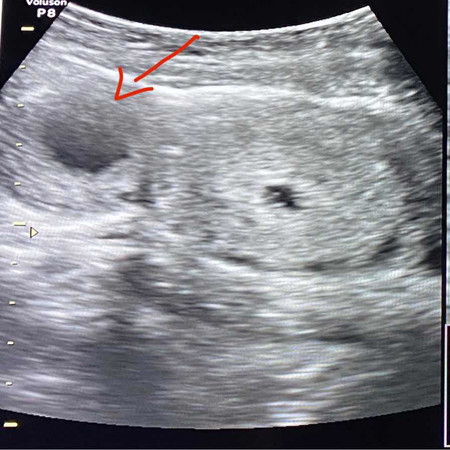

เจอซีสในรังไข่

ท้องแรกไปซาวด์มาแล้วเจอซีสในรังไข่ ตอนนี้ 7wค่ะ มีแม่ๆคนไหนเคยเป็นแบบนี้ไหมคะ คุณหมอบอกโอกาสหายเองมีตอนหลัง3เดือน รอฮอโมนส์เบาลง แต่ก็ยังรู้สึกไม่สบายใจ แม่ๆที่เคยเป็นมีวิธีดูแลร่างกายกันยังไงบ้างคะ

บ้านนี้เป็นตั้งแต่ก่อนท้องจ้า หมอเชียร์ให้รีบท้อง พอท้องได้ 3 เดือน มันยุบหายไปเองหมดเลยจ้า